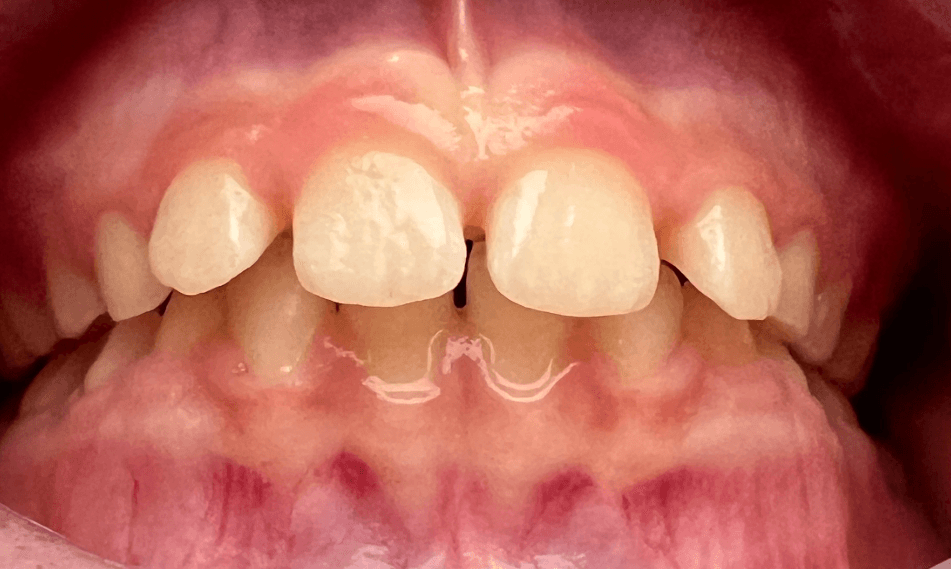

Fechamento de diastemas

Os diastemas apresentam etiologias variadas, como discrepâncias no tamanho dentário, ausência de dentes e hábitos deletérios. O uso de alinhadores para fechamento desses espaços é uma indicação bem comum, mas devemos ficar atentos a alguns detalhes.

Fechamentos de diastemas entre centrais superiores podem precisar ser acompanhados de uma frenectomia, para estabilidade do resultado